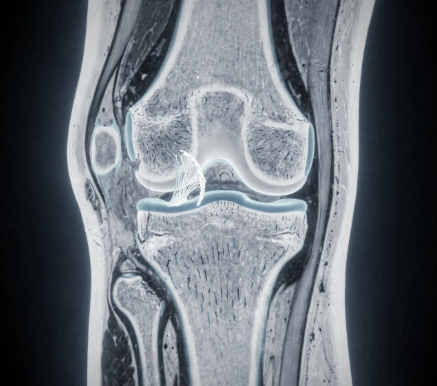

무릎 관절 안쪽에는 충격을 흡수하는 반월상연골이 위치해 있습니다.

갑작스러운 방향 전환이나 쪼그려 앉았다 일어나는 동작에서 손상되기 쉽습니다.

무릎 안쪽 통증과 함께 무릎이 걸리는 느낌, 움직일 때 소리가 나는 증상이 동반될 수 있습니다.